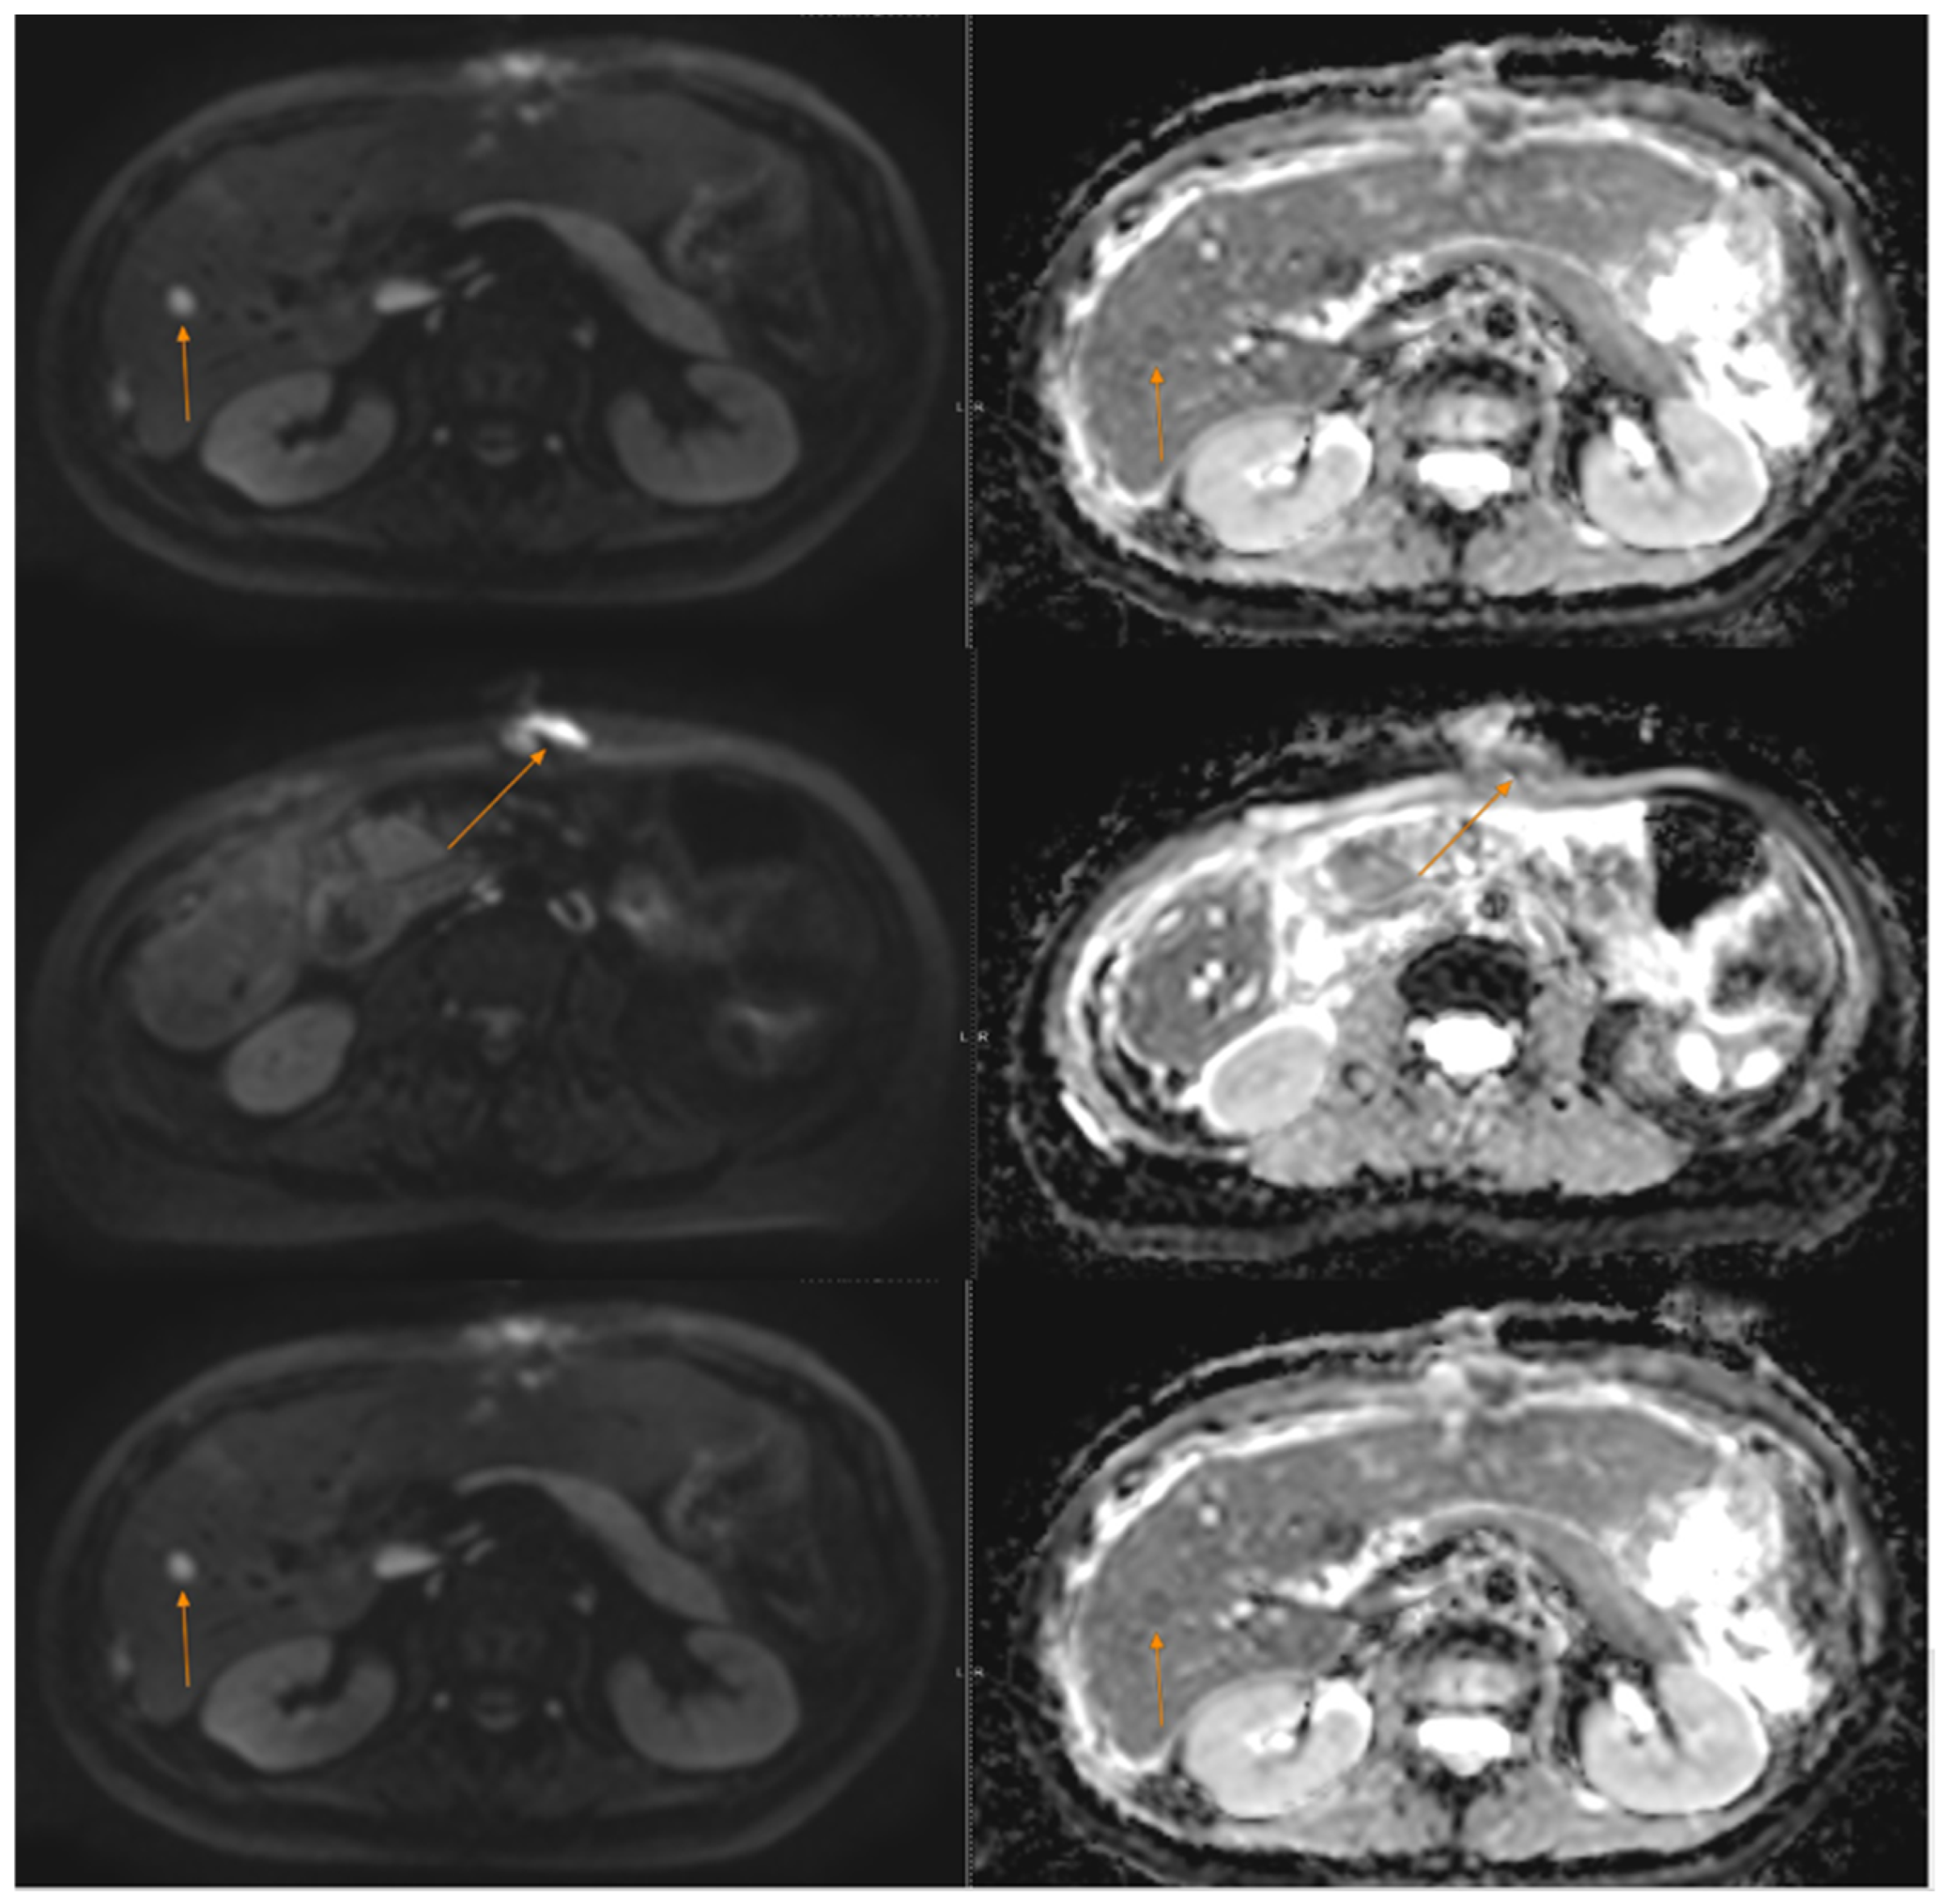

The patient was referred to our department for oncological evaluation. Given the rarity of the diagnosis and the limited data available in the literature regarding standardized adjuvant treatment protocols for GNET, a comprehensive assessment was initiated. We recommended a PET-CT scan to determine the extent of disease and assess metabolic activity, alongside repeat immunohistochemistry and molecular profiling through NGS or a Foundation One® panel. The patient was also referred to an international sarcoma/rare disease institute for a second opinion. The PET-CT scan revealed no evidence of metabolically active disease (see Figure 2). Molecular analysis via NGS/Foundation One® did not identify any actionable mutations. The tumour mutation burden (TMB) was low, microsatellite status was stable (MSS), and PD-L1 expression was negative (described in Table 2).

In February 2023, abdominal and pelvic MRI re-evaluation showed no signs of local tumour recurrence at the site of the entero–entero anastomosis. However, it revealed a 2 cm nodular hepatic lesion located at the junction of segments IVa and VIII, along with two additional smaller nodular liver lesions—one at the junction of segments VI and VII, and another within segment VIII. The imaging appearance of these lesions was inconclusive, and further evaluation was recommended, including PET-CT to assess metabolic activity and exclude tumour recurrence, liver MRI for detailed characterization, and a surgical consultation. At follow-up in our clinic, the patient maintained an excellent performance status, with normal laboratory results. Based on these findings, we recommended a liver MRI, PET-CT, and referral for surgical or interventional radiology consultation to consider biopsy and confirm possible disease progression. Subsequent PET-CT confirmed disease relapse, revealing metabolically active perihepatic peritoneal lesions—measuring up to 10 mm near segment IVa/VIII, with additional smaller lesions around segments VIII and VI–VII (with an SUVmax raging between 11–13).

Following surgical consultation, the patient underwent an atypical hepatectomy of segment IVa in May 2023, along with a biopsy of a peritoneal nodule. The procedure was performed for diagnostic purposes and appeared to achieve macroscopic clearance (R1 resection). Final histopathological and immunohistochemical analysis confirmed liver and peritoneal metastases of GNET/CCS, with PD-L1 expression showing a tumour proportion score (TPS) of 15%. Unfortunately, a postoperative MRI revealed two liver metastases showing dimensional progression. A second NGS analysis performed on the liver metastasis did not reveal any additional actionable genetic alterations for treatment selection. The tumour remained microsatellite stable (MSS), with a tumour mutational burden (TMB) of 4 mutations/Mb and confirmed the presence of the EWSR1-CREB1 fusion. PD-L1 expression remained at 15% TPS. The discrepancy of the initial and subsequent molecular tests may reflect tumour evolution over time or technical variability in molecular testing and highlights the dynamic biology of these ultra-rare malignancies. Subsequent PET-CT confirmed progression, with active peritoneal and liver lesions (the hepatic lesion had an SUVmax of 12.4, and the largest peritoneal nodule an SUV max of 11.5). The patient then sought further follow-up and management at another clinical centre, with recommended cytoreductive surgery followed by a combined regimen of immunotherapy and targeted therapy—specifically, nivolumab and cabozantinib. Chemotherapy was considered a secondary option, to be pursued only if the patient was unable to access first-line targeted treatment due to lack of reimbursement by the National Health Insurance Program. Literature data suggest that GNET/CCS cases may respond to various targeted agents, including MET kinase inhibitors (such as crizotinib, cabozantinib, or tivantinib), VEGFR inhibitors (such as pazopanib or sunitinib), and immune checkpoint inhibitors. The therapeutic options we proposed were based on an individualized approach, incorporating the patient’s molecular and tumour-specific characteristics. These included PD-L1 expression of 15% (TPS), presence of the EWSR1-CREB1 fusion, absence of other actionable oncogenic drivers, and a Ki-67 index of 30%. Our decision was guided by case-based evidence from the literature, with the rationale that cabozantinib, a multi-kinase inhibitor, may provide a clinically meaningful response, as well as that co-administration with a PD-1 inhibitor (nivolumab) could counteract T-cell exhaustion, potentially producing a synergistic antitumor effect [19,20]. Due to rapid progression of liver and peritoneal metastases, with minimal response to prior local therapies and a high risk of further disease advancement, achieving a rapid therapeutic response was deemed essential.

Figure 2. Postoperative PET-CT-no residual disease.